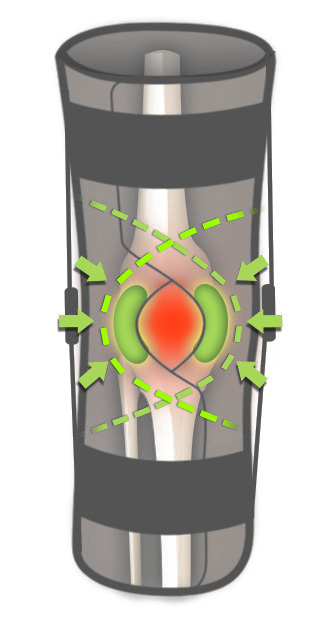

Każda orteza z serii IB jest wyposażona w dwie wyprofilowane peloty, które wzmacniają i stabilizują rzepkę.

Każda orteza z serii IB jest wyposażona w dwie wyprofilowane peloty, które wzmacniają i stabilizują rzepkę.